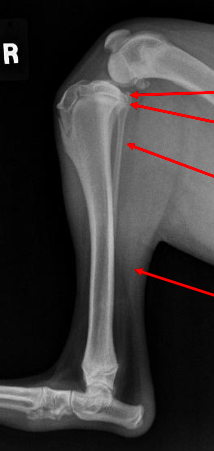

what phase of bone healing is this and why?

stage 1-2: there are sharp fracture margins

35

stage 3: can see callus formation and the margins of the fracture become less sharp and more hazy

36

stage 4: there is remodelling, a thickened callus, and the gap is nearly closed

37

what stage of fracture healing is this and why?

stage 5, can't see the fracture anymore and the callus has been reduced almost completely